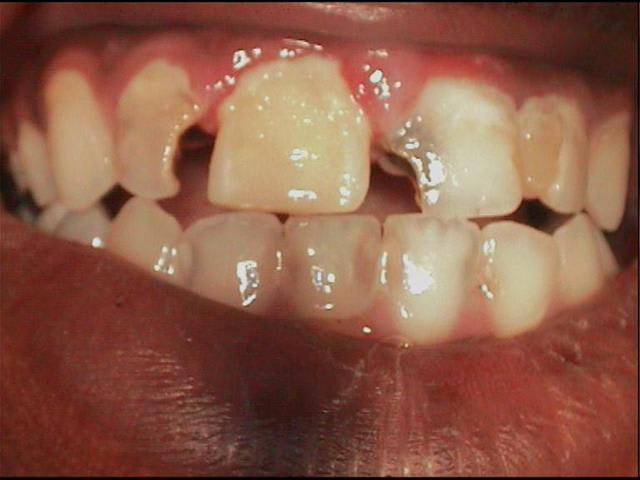

13 ans, je vous livre en vrac et dans n'importe quel sens

je m'en vais donc naviguer quelques temps entre pulpites et nécroses, calmer les pleurs, resorber les granulomes, ré équilibrer le "risque carieux"

j'ai passé les détails, aucune dent indemne de toute manière, tout est comme ça , les inc md itou

techniquement je dois etre loyal, les photos font reculer, j'ai reculé aussi en bouche, mais c'est plus impressionant au premier abord, dans le détail tout peut se jouer comme le montre cette radio

alors: les pulpites et granulomes en prems, ensuite les endos inévitables, ensuite des verre iono ou eugenates partout, ré équilibrer le risque et motiver, ensuite caler l'occlusion avec les 8 pm dans un premier temps(parceque là j'y pige rien) ensuite l'ortho (parceque là c'est pas présentable)enfin toutes ces sortes de chose quoi...